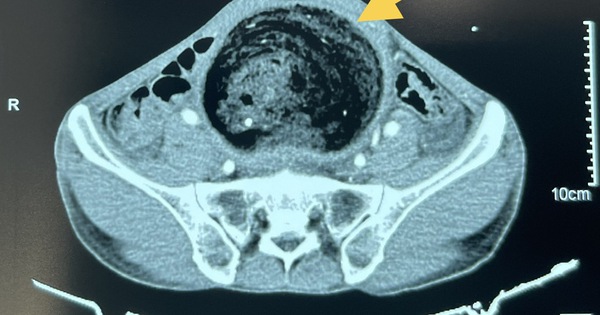

Khối phân kích thước lớn trong đại trực tràng bệnh nhân. Ảnh: BVCC.

Qua thăm khám tình trạng bụng, các bác sĩ phát hiện khối bất thường kích thước 20x 30cm; mật độ chắc. Trên hình ảnh cắt lớp vi tính bụng: khối bất thường là khối phân tích tụ lâu ngày tại đại tràng sigma gây giãn toàn bộ khung đại tràng. Đường kính quai đại tràng giãn lớn nhất là 12cm.

Bệnh nhân đã được bù dich điện giải, nuôi dưỡng tĩnh mạch trước mổ. Trong mổ thấy toàn bộ khung đại tràng giãn lớn đường kính >10 cm; thành dày; trương lực có giảm. Khối phân kích thước khoảng 20 x 30 cm ở đại tràng sigma.